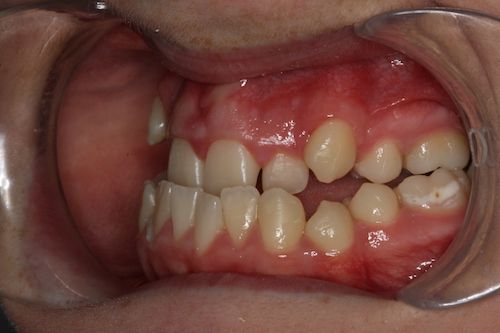

When the bones of the face and jaws are out of balance with each other, orthodontics alone will often not be able to position the teeth in order to create a functional bite. This imbalance between the jaws can result in a combination of problems. These may include:

- Crowded, irregular teeth